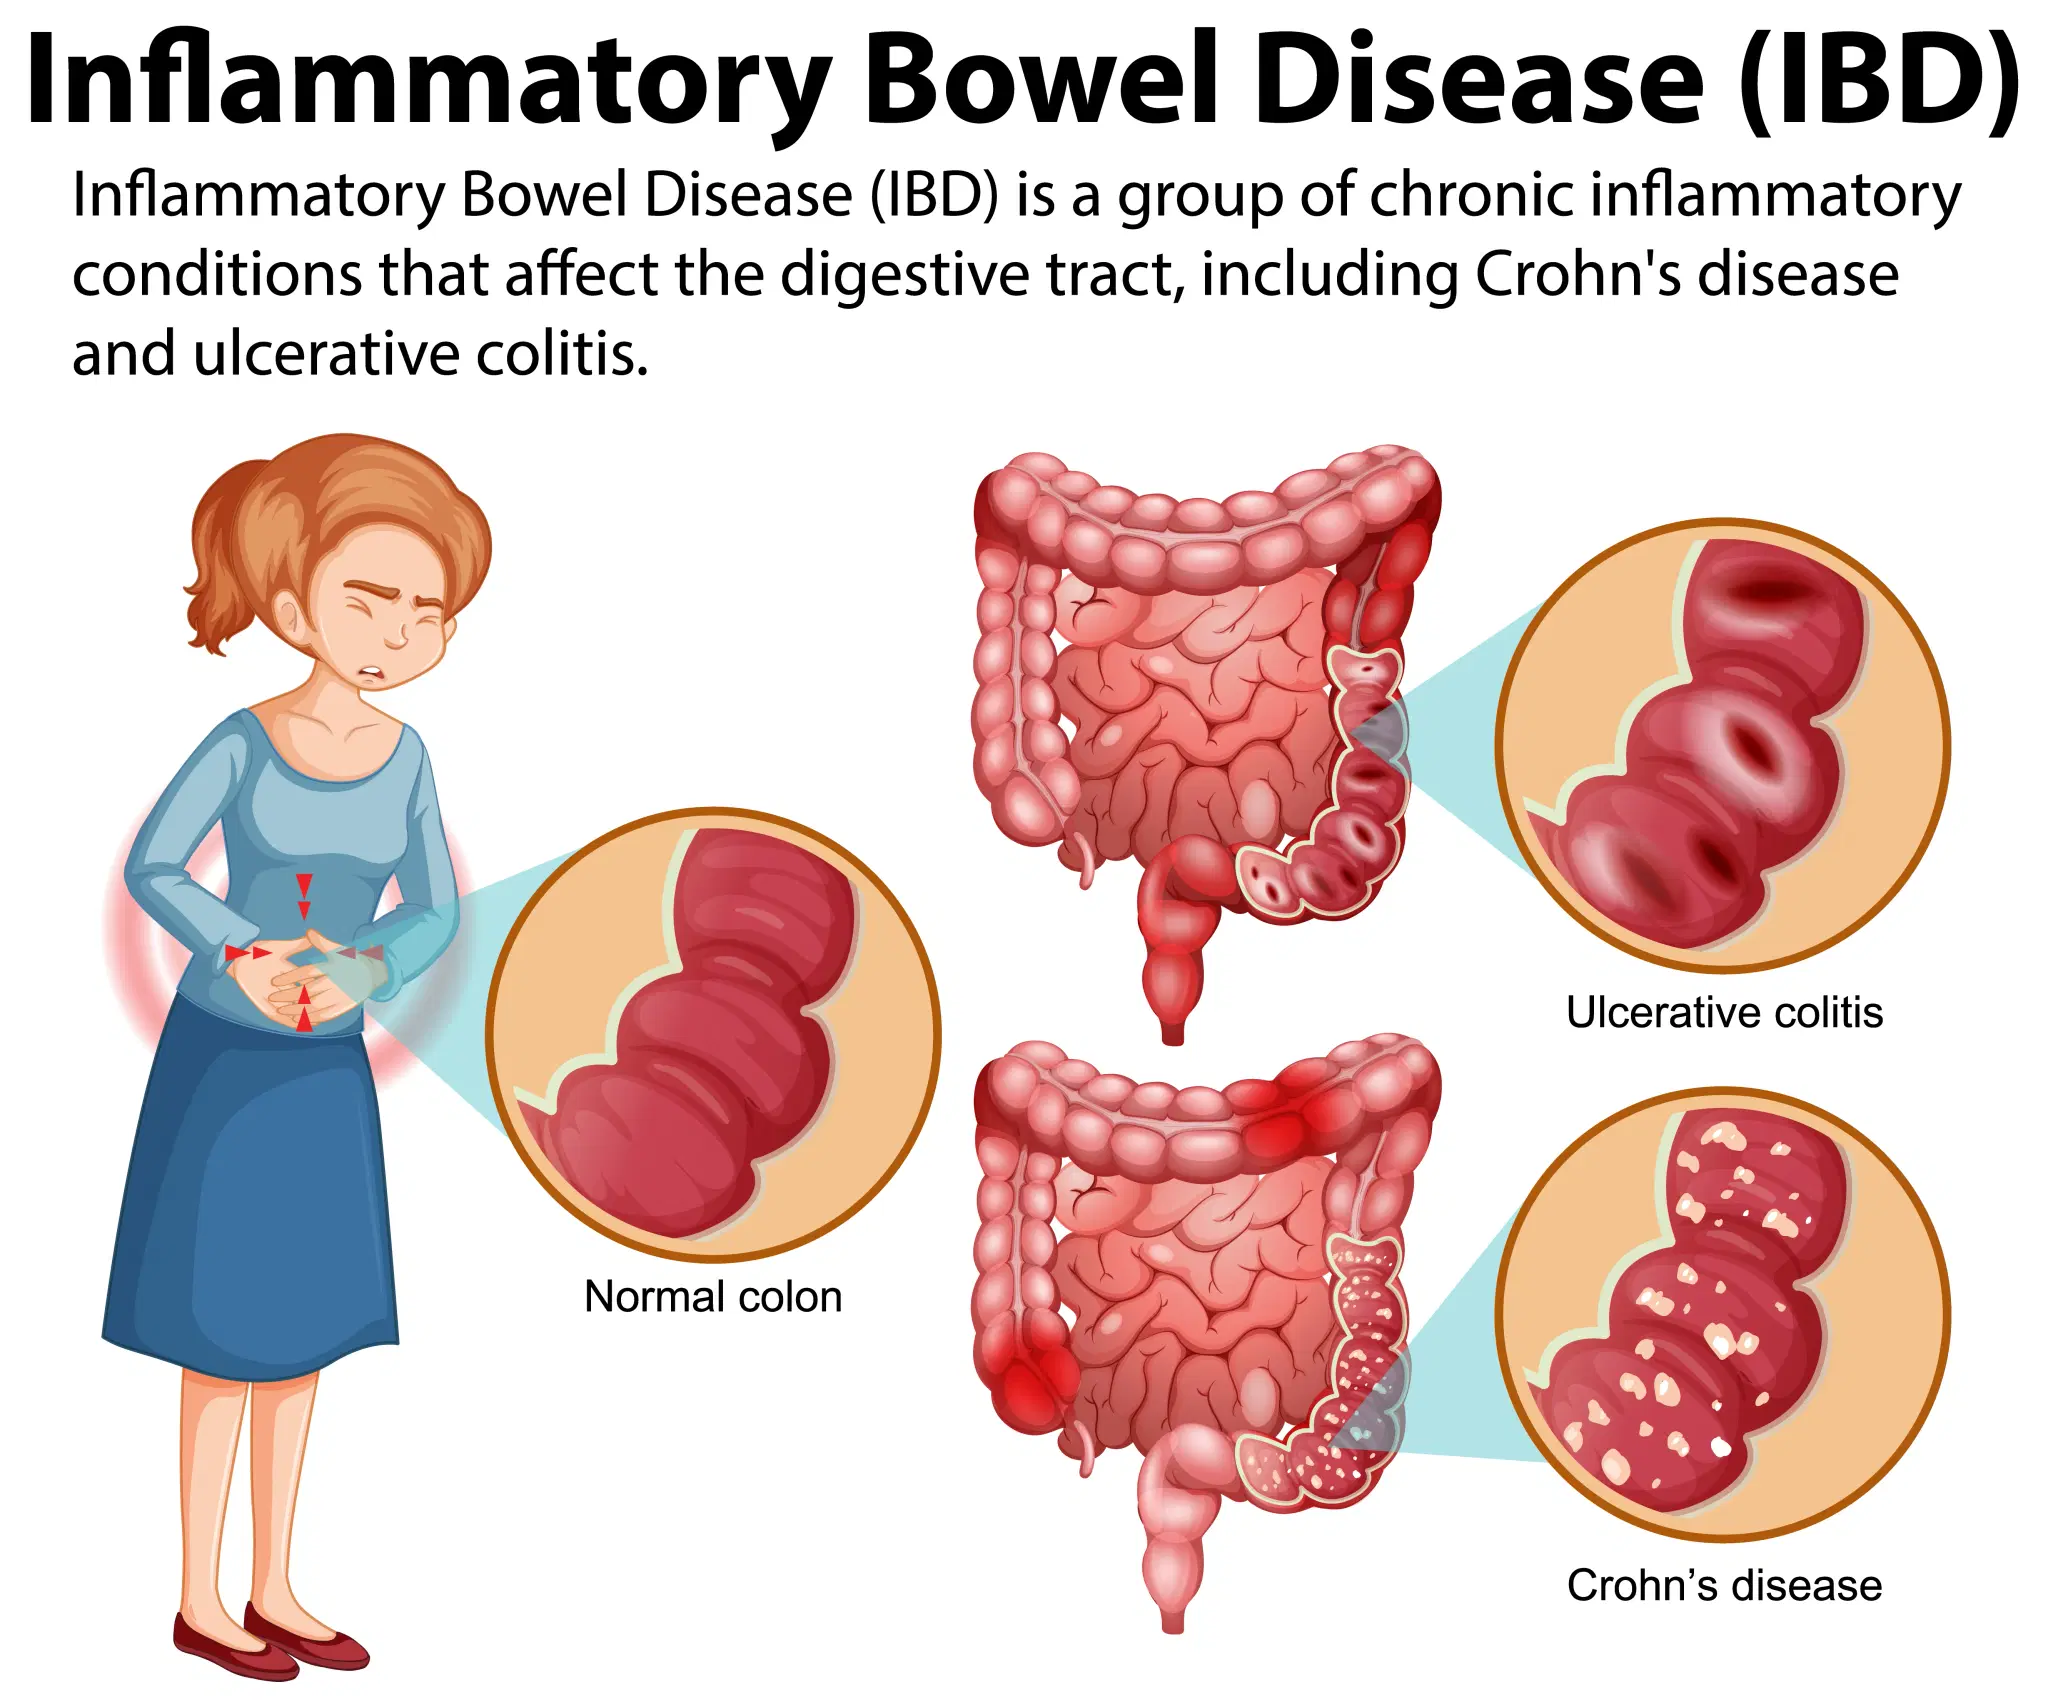

Inflammatory Bowel Disease (IBD)in Vijayawada

The IBD subspecialty focuses on chronic inflammatory diseases of the digestive tract, including Crohn’s disease and ulcerative colitis. Our expert gastroenterologists provide comprehensive, long-term care tailored to each patient’s needs. Key procedures include colonoscopy with biopsy, small bowel capsule endoscopy, and the administration of advanced biologic therapies. Using high-definition endoscopy, chromoendoscopy, and therapeutic drug monitoring, we ensure accurate diagnosis and effective treatment. Our approach emphasizes improving quality of life, preventing complications, and managing issues such as strictures and fistulas. We also offer nutritional counseling, recognizing the vital role of diet in controlling symptoms and supporting overall health.

Inflammatory Bowel Disease Treatment in Vijayawada

At Vijayawada Gastro Centre, we offer specialized care for Inflammatory Bowel Disease, including Crohn’s disease and ulcerative colitis. Our expert gastroenterologists use advanced diagnostics such as colonoscopy, biopsy, small bowel imaging, and therapeutic drug monitoring to accurately assess disease severity. Treatment plans include medications, biologic therapies, nutritional guidance, and long-term disease management. We focus on reducing inflammation, preventing complications, and improving quality of life. With personalized care, modern endoscopy technology, and continuous monitoring, our team ensures effective and compassionate treatment for patients living with chronic IBD in Vijayawada.